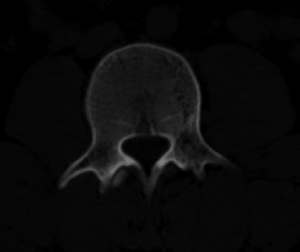

男,20,士兵,腰痛3年多,无外伤史

考虑:1、多发许莫尔氏结节形成;

2、建议平行腰5椎体扫描或冠矢状曲面重建除外椎弓峡部断裂。

倒数7~9幅图像示椎体后缘双边征及双关节征,支持l5轻度滑脱。

1、多发许莫尔氏结节形成;

2、椎弓峡部断裂。

3、l5轻度滑脱。

1、多发许莫氏结节。

2、腰5双侧椎弓峡部崩裂并i度前滑脱,楼主椎间盘扫描角度有问题,另外需要反倾角扫描腰5椎弓峡部。

2、腰5双侧椎弓峡部崩裂并i度前滑脱。